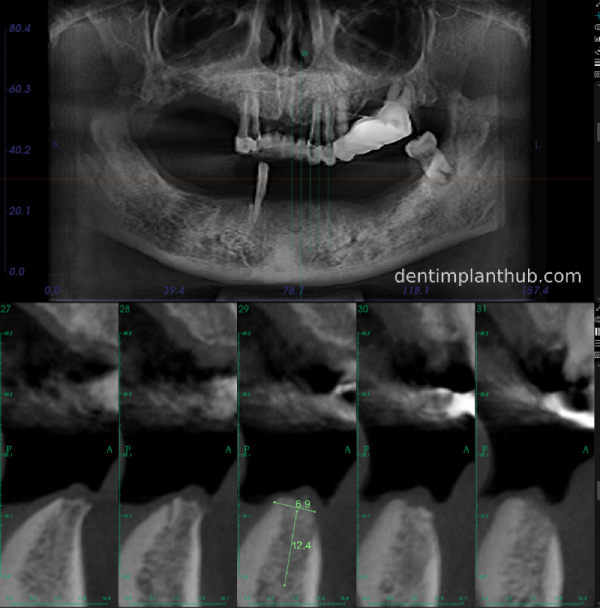

A review of the CBCT on 6/10/23 was more promising and a surgical plan was subsequently drawn up.

46

44

42

32

34

36

General schematic of the surgical programme

Detailed list of implant types and composite abutments to be prepared.

46 tooth position, implant model number 4810, RC series straight composite abutment;

44 tooth position, implant model number 4110, RC series straight composite abutment;

42 tooth position, implant model number 4110, RC series straight composite abutment; alternate implant model number 3310, alternate NC series straight composite abutment;

32 tooth position, implant model number 4110, RC series straight composite abutment; alternate implant model number 3310,. Alternate NC Series Straight Composite Abutment;

34 Dental Position, Implant Model No. 4110, RC Series Straight Composite Abutment;

36 Dental Position, Implant Model No. 4808, RC Series Straight Composite Abutment;